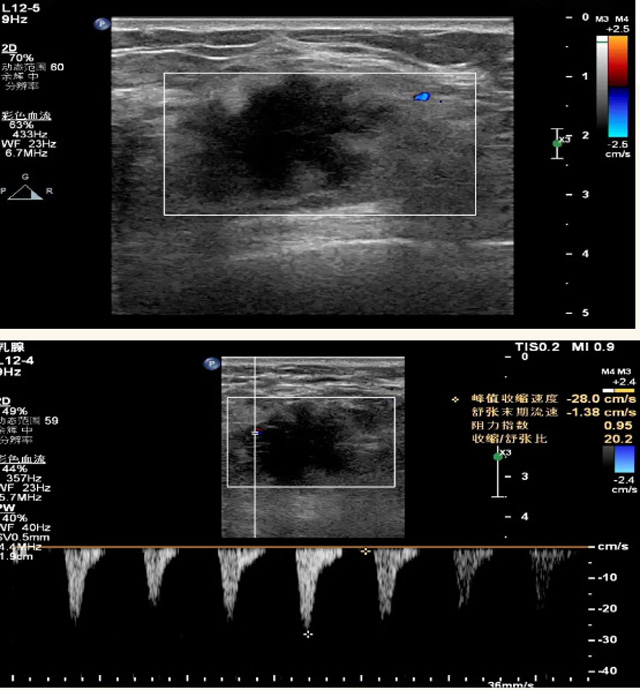

乳腺B超檢查無(wú)輻射,對(duì)囊性病變敏感,可以實(shí)時(shí)觀察病灶。超聲引導(dǎo)活檢跟手術(shù)前的定位。就是它對(duì)于微小的鈣化查出率比鉬靶稍微差點(diǎn)。磁共振MRI檢查也是是沒(méi)有輻射的,對(duì)備孕跟已經(jīng)懷孕的人士比較友好。不用擔(dān)心這個(gè)輻射影響胎兒?jiǎn)栴}。對(duì)乳腺病灶敏感性較高,致密乳腺病灶、乳腺癌的復(fù)發(fā),準(zhǔn)確鑒別囊性及實(shí)性病變。可以幫助臨床醫(yī)生判斷惡性、良性病變。但是MRI磁共振對(duì)微小鈣化不明顯,微鈣化還是鉬靶靠譜點(diǎn)。檢查時(shí)間比較長(zhǎng),有偽影的影響。費(fèi)用相對(duì)B超,鉬靶高很多。